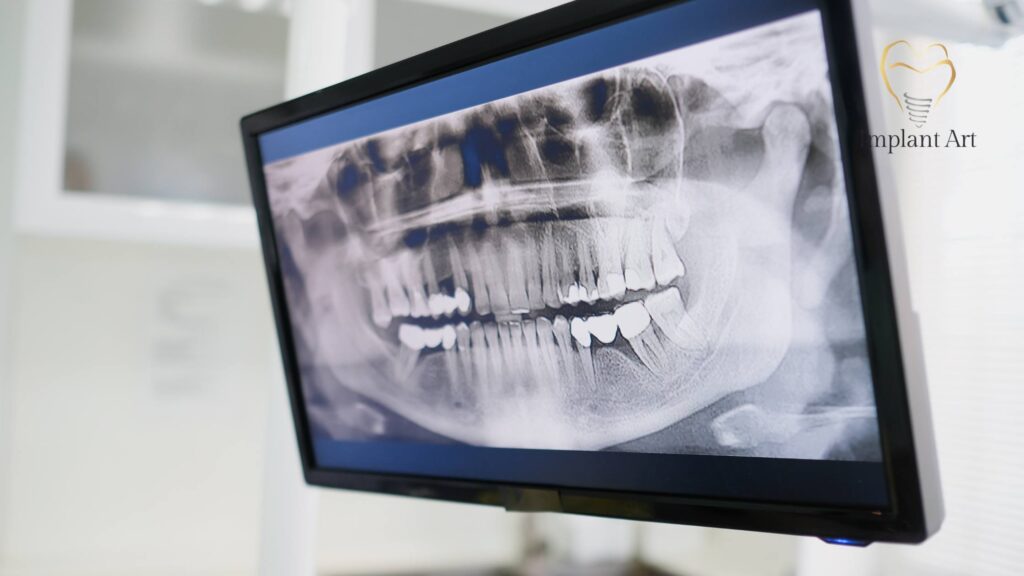

1. Advanced 3D Planning

We use Cone Beam CT (CBCT) scanning to capture detailed 3D images of your bone, nerves, and tissues. This digital map allows us to plan exact implant positions before surgery, minimising risk and reducing trauma.